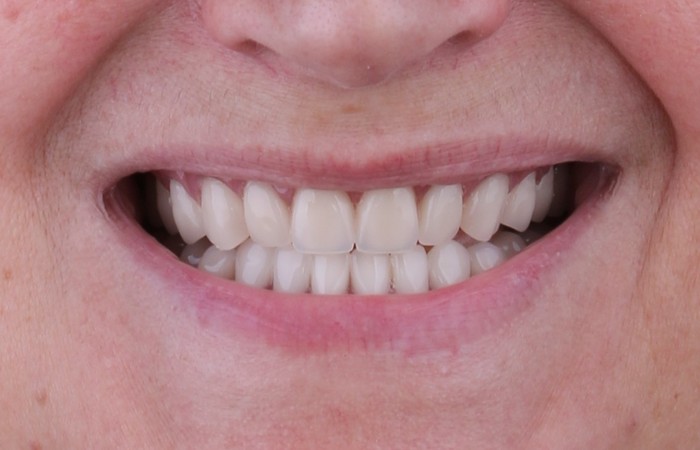

Дорогие друзья, вы должны понимать, что не страшен ни большой объем работы, ни удаление всех зубов, ни костные пластики, ни количество установленных имплантатов. Страшно лишь то, что одно маленькое «потерплю», может вылиться в большое «надо было еще вчера». Чем больше и дольше вы терпите, тем объёмнее и продолжительнее получится ваше лечение. Почистив вовремя зубы, можно не допустить кариес. Залечив кариес на начальных стадиях, вы избавите себя от его осложнений в виде, к примеру, пульпита или периодонтита. Вылечив вовремя пульпит или периодонтит, удаление зуба обойдет вас стороной. Своевременное восстановление утраченного зуба, убережет вас от костных пластик и т.д. После всего этого говорить о том, что своевременное обращение к стоматологу, да и к любому другому доктору, оградит вас от ненужных нервов и трат, думаю нет смысла. Тут и так все понятно без слов. Поэтому чистите зубы, подтягивайтесь и давайте встречаться чаще на профилактических осмотрах, чем при проблемах с зубами.

На самом деле в этом нет ничего опасного. Вашему здоровью и уж тем более жизни ничего не угрожает. Более того никто без зубов из клиники вас не отпустит. Перед удалением в обязательном порядке ортопедом снимаются слепки челюстей, а после, техником в лаборатории изготавливаются полные съемные протезы. После того, как работа попадет в клинику, пациента записывают на удаление зубов, а следом сразу на примерку и сдачу конструкции в виде временных протезов. Это значит, что как вы пришли в клинику с зубами, так с зубами из нее и уйдете.

В случае с этой пациенткой изготовление отдельного хирургического шаблона не требуется. Ортопед при помощи фрез формирует подобные отверстия в самом временном протезе, который и будет выполнять функцию шаблона. После того, как операция проведена тот же доктор заделает эти отверстия специальным материалом и можно будет дальше пользоваться протезом до момента изготовления постоянной конструкции. И нет, класть его в стакан с водой перед сном будет ненужно.